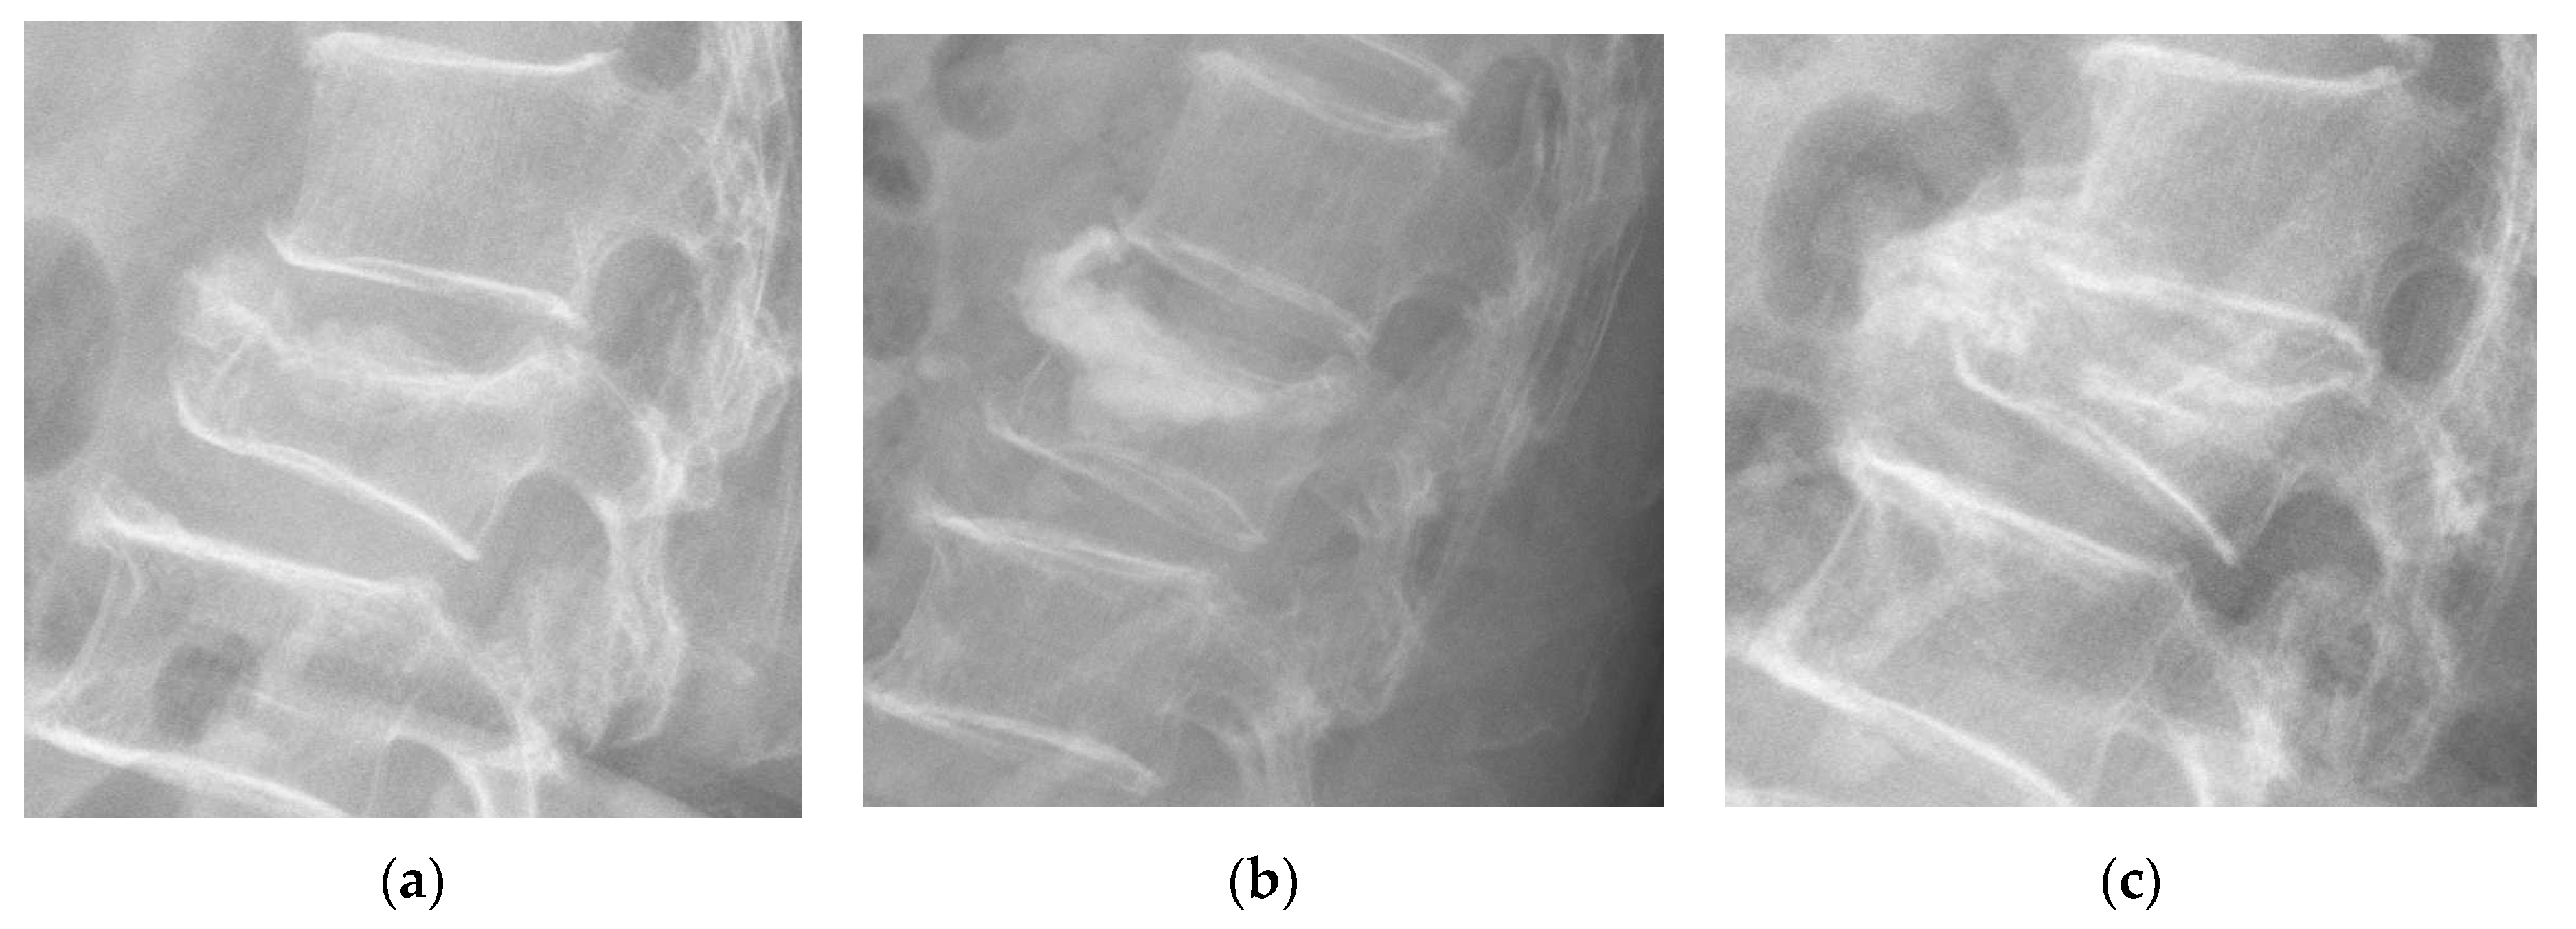

2.2. Measurement of Vertebral Parameters and New Bone Formation

4.2. New Bone Formation